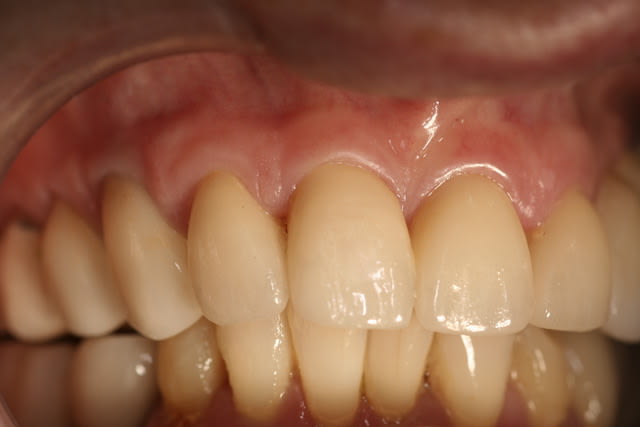

Je crois qu'effectivement la CAO peut être chiante, moi ça m'éclate. Il y a du boulot pour toutes les préférences et le travail de molinarius réunit le meilleur des deux mondes.

c'est du beau travail jumpingjack !

oui c'est du beau travail ..

Cependant je suis sure que ces types de cas ne se réalisent pas en deux temps trois mouvements!

il y du temps d'usinage , beaucoup de modelage pour parvenir à de tels cas et autant pour la finition .. donc on en revient toujours au même .. le temps que vous passez dessus vous ne le passez pas au fauteuil ...secu ou pas , votre rentabilité est ailleurs..

Sur le 1er cas de jump.... reconstitution au maxillaire , il y a plusieurs usinage(quelques heures) et un certain de temps finition à la pièce à main ... et sur d'autre plusieurs cuisson de maquillage sans doute ...

Que certains prats soient doués à jouer les prothésistes ;) c'est une chose mais je suis sure que c'est plus par plaisir de faire de la prothèse :) plutôt qu'un intérêt financier ... je me trompe jumpingjackflash ?